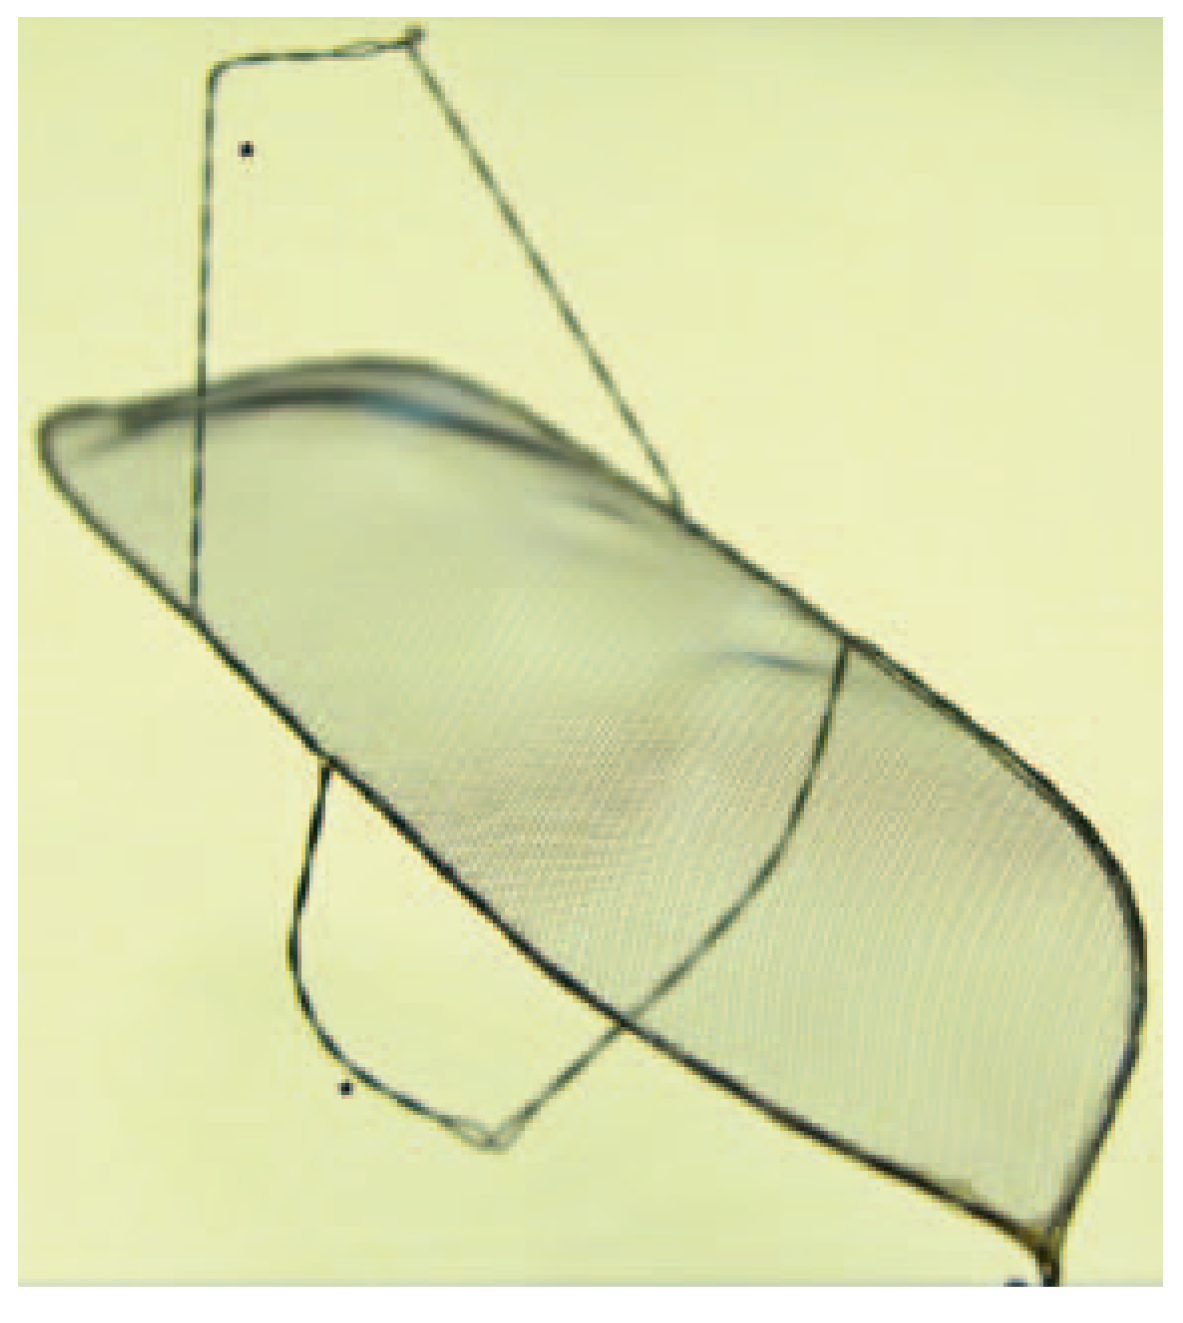

Figure 2. Keystone Heart Embolic Deflection Device. The device consists of the deflection shield and two nitinol hoops (*). (Courtesy of Keystone Heart Ltd, Herzliya, Israel.

The EDD (Keystone Heart Ltd, formerly SMT Research & Development Ltd, Herzliya, Israel) is introduced via femoral access (Figure 3). It is a very similar device as the Embrella, also deflecting rather than capturing emboli (Figure 2). However there are some important differences: The device fits through a 7 French sheath, however, a 9 French sheath is often used, to facilitate recapturing of the device and allowing simultaneous placement of a pigtail through the same sheath. The device is self-positioning at the outer curvature of the aortic arch covering all three neck vessels. It is anchored in the brachiocephalic trunk and the inner curvature of the aorta by stabilizing nitinol arms. Femoral access and minimal interference with the brachiocephalic trunk are potentially less traumatic than advancing a device through the brachiocephalic trunk.